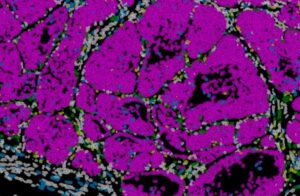

Credit: Instituto de Neurociencias UMH CSIC

To reach these conclusions, the team combined mouse genetic models, single-cell analyses, chromatin studies, and spatial transcriptomics techniques that allow researchers to observe the organization and behavior of cells directly within the tumor tissue. The processing and analysis of the large datasets generated from thousands of cells was led by bioinformatics expert from Nieto’s team, researcher Nitin Narwade. In addition, in collaboration with Professor Gema Moreno Bueno from the Universidad Autónoma de Madrid and the MD Anderson Cancer Center Spain Foundation, the researchers analyzed breast cancer patient samples and detected similar patterns of Prrx1 expression, suggesting that the mechanism described could have direct relevance for tumor classification and clinical prognosis.